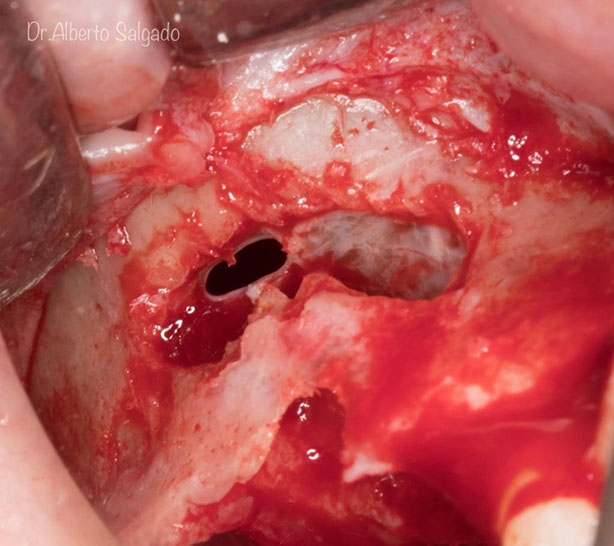

Dr. Alberto

Salgado